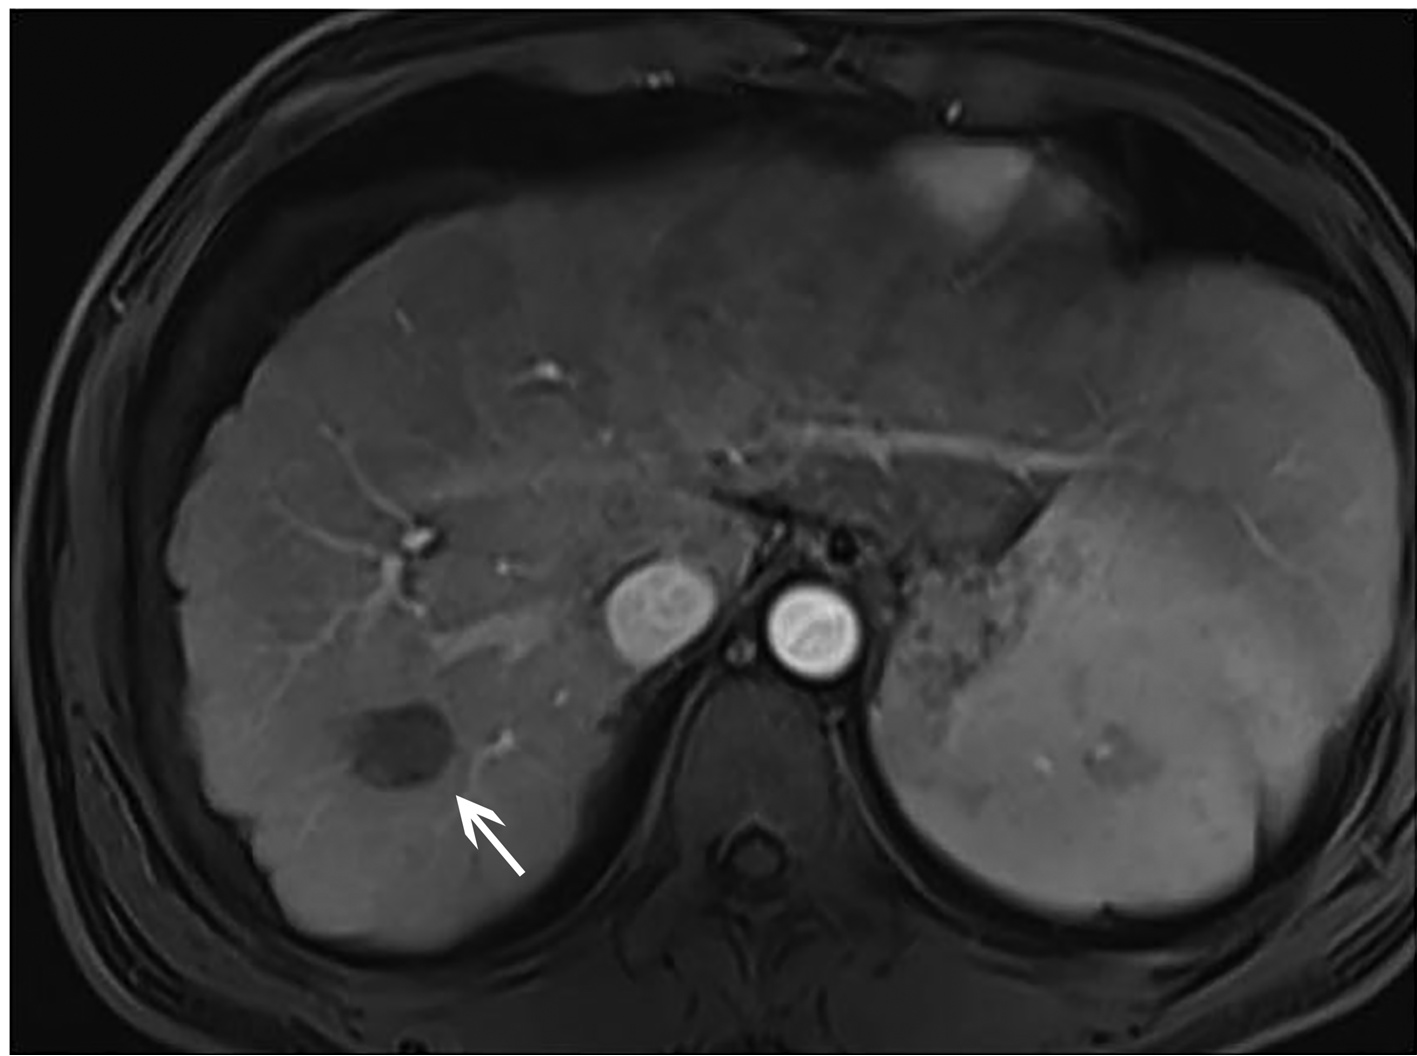

乙型肝炎肝硬化上消化道出血的ΔCT特征性表现及预测模型的建立

李俊杰, 孙岩岩, 李将宏, 郑虹

2022, 38(5): 1081-1085. DOI: 10.3969/j.issn.1001-5256.2022.05.020

摘要(1053) HTML (308) PDF (2671KB)(64)

摘要:

目的  本研究旨在寻找乙型肝炎肝硬化CT特征,建立肝硬化上消化道出血预测模型,预测出血风险。  方法  回顾性分析2015年1月—2021年6月天津市第一中心医院101例型肝炎肝硬化患者的数据,将其分为上消化道出血组(P=58)及非出血组(n=43)。比较两组间实验室检查以及强化CT检查测的平扫期、动脉期、门脉期以及静脉期的CT值,并计算各期间CT值的变化(ΔCT)。计量资料两组间的比较使用t检验或Mann-Whitney U检验;使用logistic回归分析方法,预测相关危险因素;通过计算受试者工作特征曲线下的面积评估模型辨别力,而模型校准则通过Hosmer-Lemeshow确定。在多变量logistic回归分析结果的基础上,使用Rstudio4.1.2软件的R包构建预测的列线图模型,并绘制相应的ROC曲线、校准曲线以及临床决策曲线。  结果  非出血组血清TBil、WBC、PLT水平与出血组比较,差异均有统计学意义(P值均<0.05);两组在肝-Plain、脾-P-Plain、脾-P-A ΔCT值存在统计学差异(P值均<0.05)。单因素logistic分析结果显示,白细胞(OR=0.770,95%CI:0.624~0952, P=0.016)、血小板(OR=0.979,95%CI:0.965~0.994, P=0.006)、肝脏平扫期(OR=1.142,95%CI:1.058~1.233, P=0.001)、脾脏门脉期-平扫ΔCT值(OR=0.979,95%CI:0.959~1.000, P=0.050)、脾脏门脉期-动脉期ΔCT值(OR=0.979,95%CI:0.944~0.994, P=0.015)在乙型肝炎肝硬化患者发生上消化道出血与未出血两者之间差异具有统计学意义。多因素logistic分析结果显示血小板(OR=0.968,95%CI:0.944~0.993, P=0.011)、肝脏平扫期(OR=1.148,95%CI:1.047~1.259, P=0.003)、脾脏门脉期-动脉期ΔCT值(OR=0.951,95%CI:0.908~0.995, P=0.030)为上消化道出血的独立危险因素。基于多因素logistic分析结果,构建了乙型肝炎肝硬化上消化道出血的预测模型并绘制校准曲线。该模型的受试者特征曲线下面积为0.801,cut-off值为0.433,其对应的敏感度是81.4%,特异度是77.6%。模型的校准曲线与理想曲线贴合良好。  结论  乙型肝炎肝硬化肝脏具有特殊的ΔCT变化,通过ΔCT构建的预测模型对于乙型肝炎肝硬化上消化道出血具有良好的预测能力。